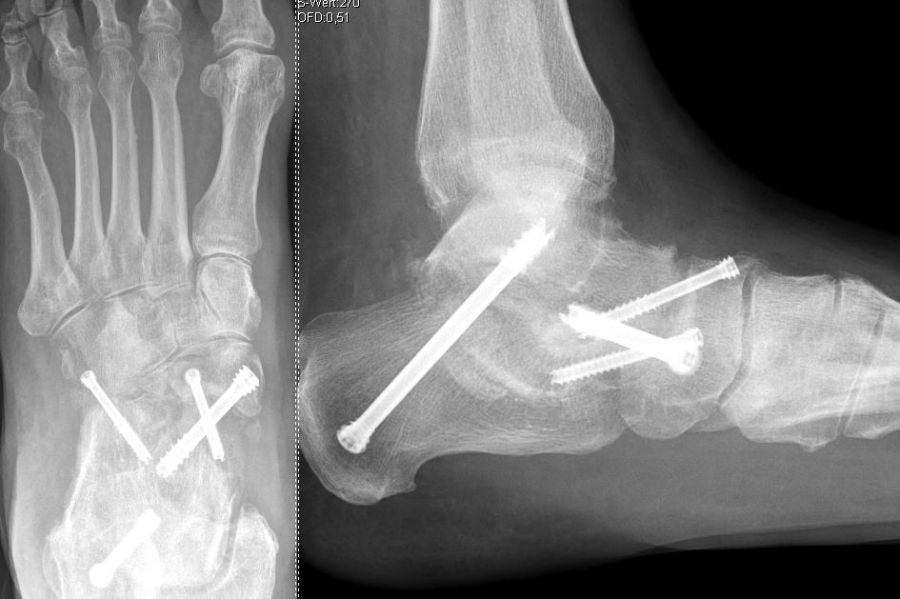

Es kommen verschiedene technische Möglichkeiten der operativen Versorgung in Frage.  Verwendung finden vor allem winkelstabile Plattensysteme, Schraubenosteosynthesen, Klammern, intraossäre Nagelsysteme, temporäre Kirschnerdraht-Transfixationen, Einbolzen von trikortikalem Span und Anlagerung von Spongiosa aus dem Beckenkamm oder dem Tibiakopf  (Abb. 2 und 3).

Die Operation erfolgt meist über einen medialen Zugang. Nach Entknorpeln der  Gelenkflächen und Anfrischen des subchondralen Knochens kann die Arthrodese mit Schrauben oder Plattensystem erfolgen (Abb. 5). Bei Fehlstellungen muss diese vor der Osteosynthese korrigiert und das Talonavikulargelenk reponiert werden. Pseuarthrosen werden hier zwischen 8-25% angegeben 3223.

Die Calcaneocuboidal-Arthrodese ist meistens Teil weiterer Arthrodesen im Bereich der Fußwurzel 34 (Abb. 10).  Eine besondere Bedeutung kommt der Calcaneocuboidal-Arthrodese bei Eingriffen zur Behandlung des Plattfußes, die der Verlängerung der lateralen Säule dienen, zu 35. Die Arthrodese kann mittels Schrauben, Klammern, Plattensystemen und ggf. der Interposition eines kortikospongiösen Spanes zur Verlängerung der lateralen Säule erfolgen.